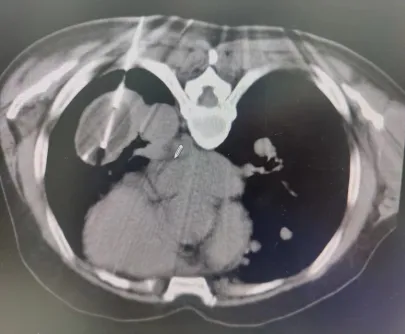

术中穿刺

患者病灶位于左下肺,大小8.5*5.6cm,患者俯卧位CT扫描定位,左下肺可见肿块影,局部麻醉后,按照手术设计穿刺路径,分别将阳极针、阴极针经皮穿刺进入病灶,通过冷消融4个循环、电解消融1个循环后,CT扫描可见肺内病灶坏死明显,手术2小时后顺利结束。术后病人无不适症状,3天后好转出院。